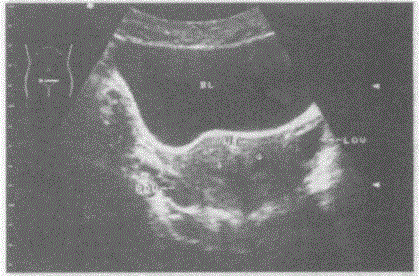

临床资料:女性,24岁,常规体检。超声综合描述:横切面子宫底部平滑,横径增宽,内可见两个宫腔内膜回声,中央有条样分隔,两部分内膜均延续至宫颈。...

问题 临床资料:女性,24岁,常规体检。 超声综合描述:横切面子宫底部平滑,横径增宽,内可见两个宫腔内膜回声,中央有条样分隔,两部分内膜均延续至宫颈。 超声提示:

选项 A.双角子宫 B.不完全性纵隔子宫 C.完全性纵隔子宫 D.鞍状子宫

答案 C